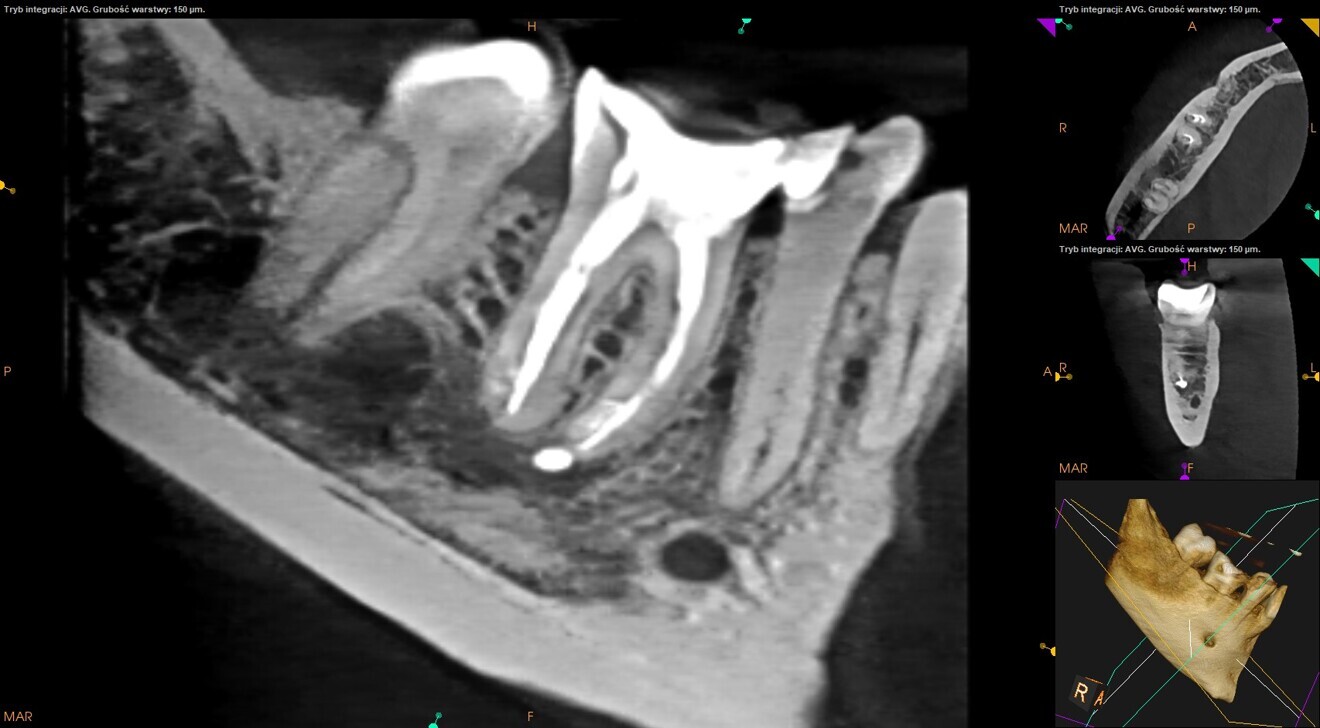

Fig. 24: CBCT scan at the six-month follow-up.

Fig. 25: CBCT scan at the 12-month follow-up.

The canals were dried with paper points and micro-suction (Fig. 21). After the irrigation protocol, there was still a lack of patency and tugback was achieved only in the mesiolingual canal. The mesiobuccal and distal canals were filled with an epoxy resin sealer and warm gutta-percha (squirting technique), and the mesiolingual canal was filled with a 30/.04 gutta-percha cone with the continuous wave of condensation technique (Fig. 22). A distally shifted periapical radiograph was performed (Fig. 23). The radiograph revealed a puff of sealer in the periapical area of the mesial root and the isthmus filled with the sealing material. A composite material was placed into the access cavity, and the patient was scheduled for the control appointment. At six months and 12 months, CBCT scans were performed (Figs. 24 & 25). The images found no signs of inflammation in the periapical area, and the tooth was asymptomatic.